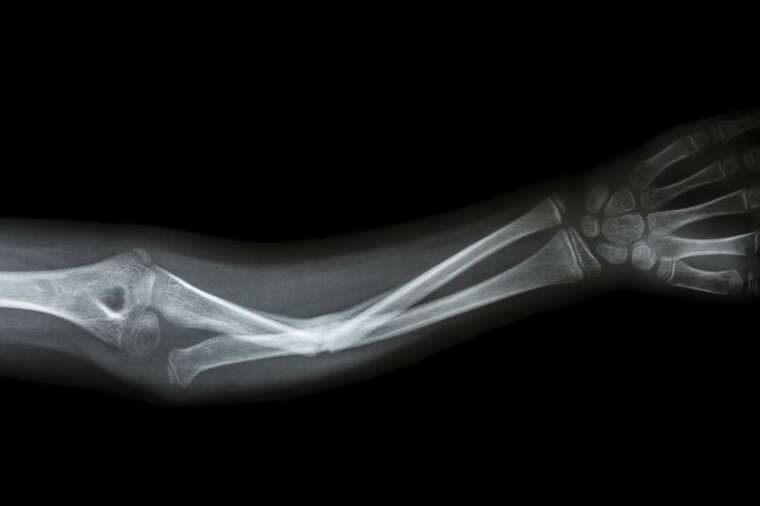

Исследование показало, что ИИ может уменьшить диагностические ошибки в отделениях неотложной помощи (от 3% до 10%).

Технологии ИИ помогут врачам быстрее ставить диагнозы, уменьшая нагрузку на персонал и повторные визиты пациентов.